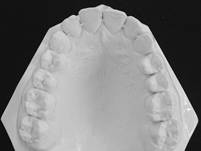

สภาพฟันก่อนรักษา

สภาพฟันหลังรักษา